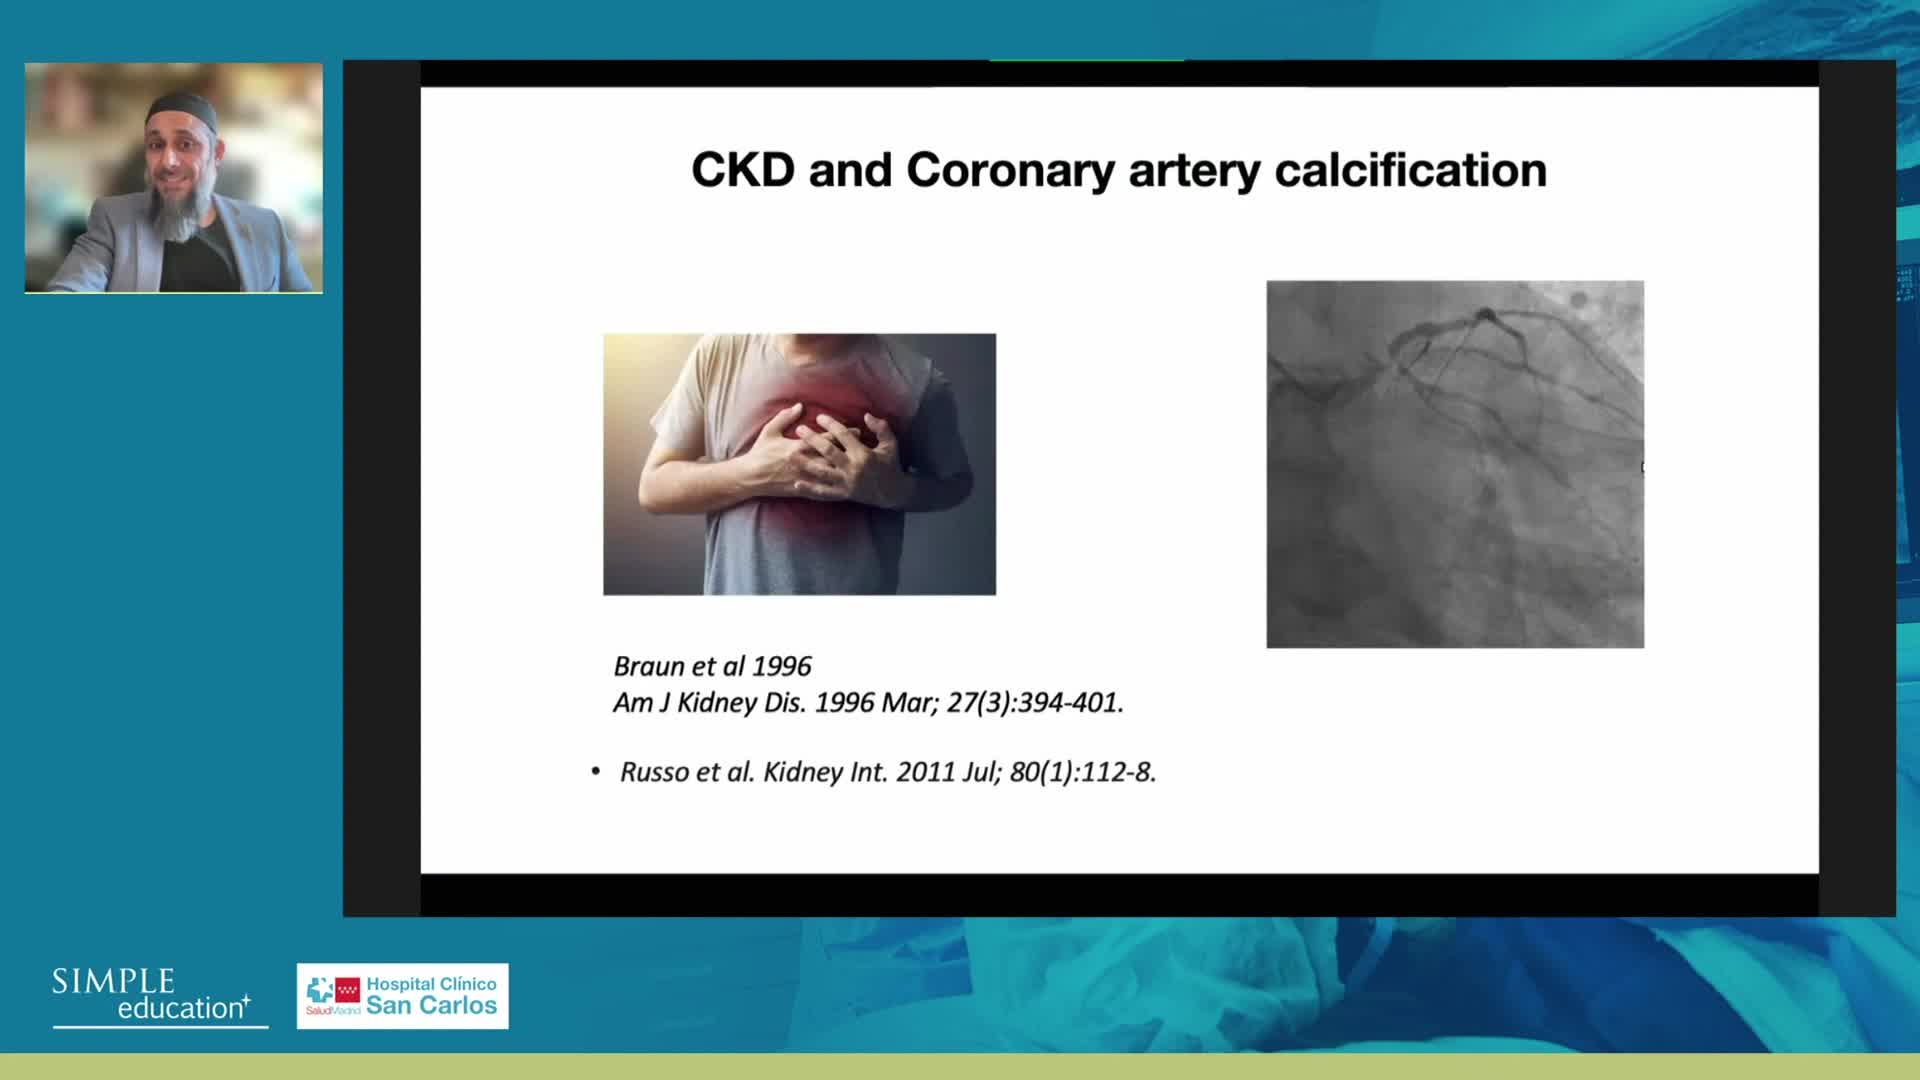

Prevention of Contrast Induced Nephropathy: Fact, Fiction and Fantasy - Christopher Baker